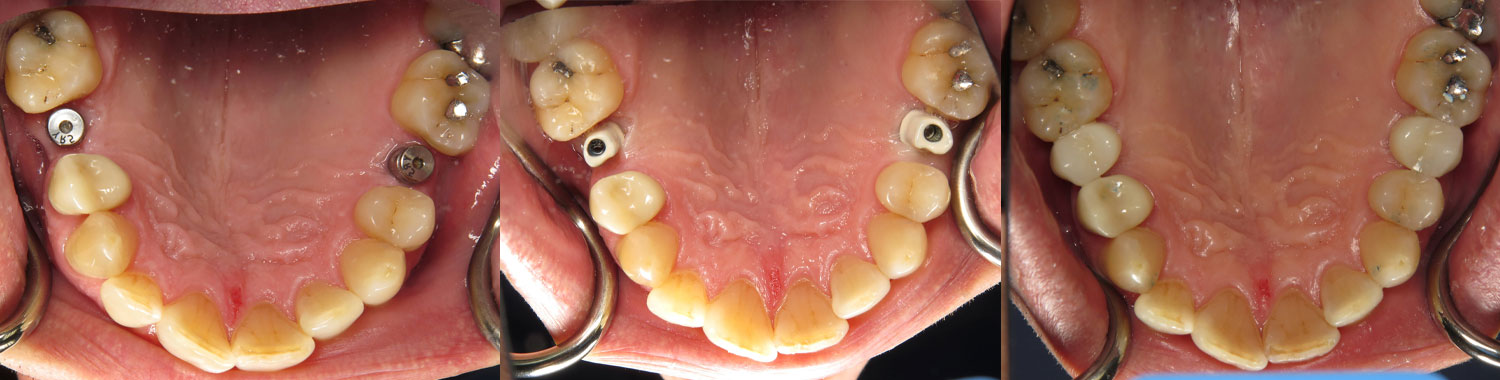

Our Dental Implant Procedure

- Implant Placement: The dental implant placement procedure is performed under local anesthesia for your comfort. Dr. Cordora will carefully place the titanium implant posts into the jawbone at precise angles and depths to ensure the stability and strength of each implant.

- Healing Period: After implant placement, a healing period of several months is required to allow the implants to integrate with the surrounding bone. During this time, temporary restorations may be placed to maintain aesthetics and function.

- Final Restoration: Once the implants have fully healed and integrated with the jawbone, custom-made dental crowns, bridges, or dentures are securely attached to the implants, completing your smile restoration.